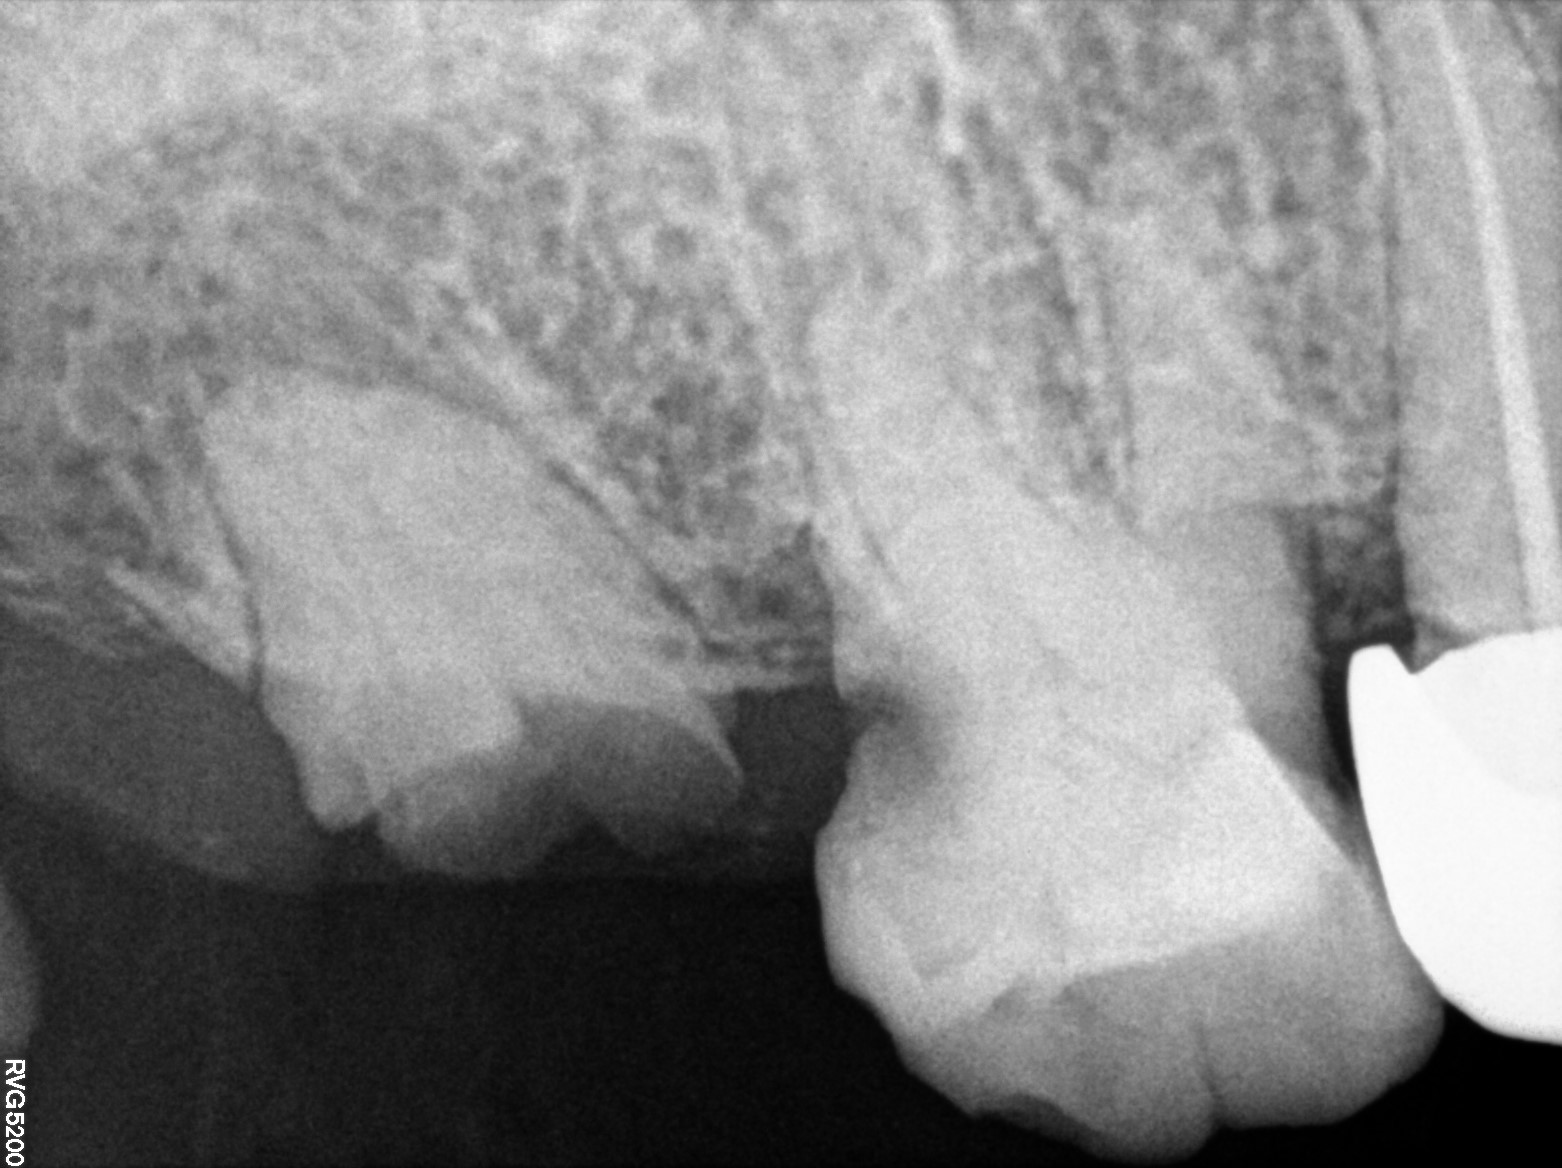

Dental Radiographs FHIR: DocumentReference · LOINC 24641-7

d (1).jpg

24641-7